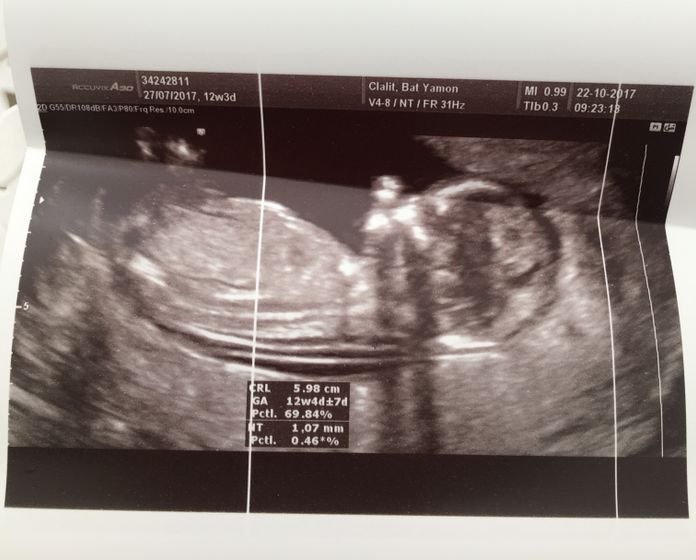

Вот и мы сегодня прошли наш первый скрининг) волновалась жуть… по УЗИ вроде всё хорошо ? врач был не русскоязычный, поэтому я толком ничего не спрашивала) единственное он уверенно сказал, что у нас мальчик и всё хорошо!!!) ктр 6см. срок 12.4 на один денёк опережаем месячные)) Риски по возврату-1:1249, а по результатам УЗИ 1:8327. Результаты анализа крови, будут аж через 2 недели. Кто делал скрининг на моем сроке? Какие у вас результаты?

У меня тоже срок был 12,4 недели. Тоже 6 см. Базовый риск трисомии 21 для 31 года 1:564, индивидуальный 1:11240 — это уже по крови, по УЗИ вроде не рассчитывали такой риск, нет такой записи.